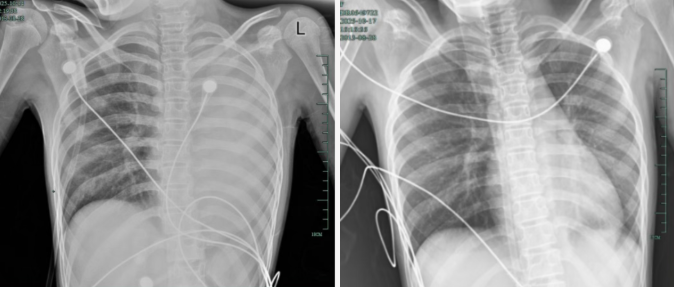

感冒、咳嗽似乎在孩子们中很常见,但12岁女孩晓晓(化名)的经历却让人心惊胆战。仅发烧一天,他的左肺就变成了“白肺”。他呼吸急促,无法躺下,血氧饱和度勉强维持在90%左右。情况非常危急!治疗前,左肺处于“白肺”状态;治疗后,“白肺”被吸收,心脏边缘清晰可见。在浙江大学第四医院儿科多学科团队的努力下,晓晓转危为安。然而,这场来势汹汹的突发事件背后却隐藏着一种很容易被忽视的慢性、严重的呼吸道疾病——塑性支气管炎。感冒咳嗽变成“白肺”的风险就隐藏在粘液里。晓晓开始出现轻微咳嗽,发烧38℃。到外医院检查显示肺炎、肺不张。当他还是变性人的时候转至浙江大学第四医院儿科后,病情急剧恶化。入院后很快出现气短、胸闷、胸痛,体温38.5℃,只能依靠5L/min面罩吸氧维持血氧。胸部X光检查显示,左肺已完全变成“白肺”,肺部炎症进展迅速。儿科副主任医师余琳根据经验判断,潇潇很可能患的是“塑料性支气管炎”。它是肺部感染的严重肺内并发症。各种原因引起的支气管异物内源性障碍,可导致支气管阻塞、通气和气体交换功能障碍。主要症状是呼吸困难、喘息、胸痛和发烧。严重时会导致危及生命的呼吸和循环衰竭。 “危险的事情是疾病是气道会被大量果冻状的粘液塞和支气管成型物堵塞,就像呼吸道被“水泥”封住一样。氧气进不去,二氧化碳出不去,痛苦随时可能发生。”多学科团队齐心协力,为支气管镜“保驾护航”,打通生命通道。由于晓晓血氧不稳定,耐缺氧能力差,手术风险很高,随时可能需要气管插管和通气呼吸机辅助。医院立即开始多学科协作,儿科、重症医学科、儿科、重症医学科呼吸与危重症护理部和麻醉科共同制定方案,最终决定进行紧急支气管镜手术。手术过程中,支气管镜一进入气道,他就看到了令人不安的一幕:气道粘膜充血,水肿,大量黄白色粘痰不断涌出,左主支气管和各肺段开口全部被粘液塞堵塞。医疗团队争分夺秒,采用负压吸引、灌洗、夹闭等技术,清除堵塞物。 “如果玻璃管被粘稠的分泌物堵住了,就拉出来清除,然后再插入。如果病人耐缺氧能力差,要及时加压、给氧……”于琳副主任医师说,经过反复操作,堵塞的呼吸道终于被打通了。手术后第二天,晓晓的呼吸困难、胸痛症状得到很大改善,病情初步得到控制。她被成功拉出“鬼门关”,转回普通儿科病房继续治疗。后续检查显示,他的感染原因是高毒力的铜绿假单胞菌。osa,通常发生在免疫功能低下的人身上。经过精准抗感染、希望、抗炎等一系列治疗,孩子逐渐恢复健康,顺利出院。幸运的是,潇潇的“白肺”通常都被吸收并恢复正常,没有留下任何严重的并发症。如果您的孩子出现这些症状,请注意不要拖延,尽快就医!于林医生介绍,塑性支气管炎是儿童时期危险的呼吸道急症。它常见于2至12岁的儿童,通常由病毒或细菌感染引起,例如流感病毒、肺炎支原体和腺病毒。其特点是起病隐匿、进展快、易误诊、漏诊。如果不及时治疗,会留下闭塞性细支气管炎、支气管扩张等后遗症,严重时可危及生命。家长一定要警惕这些症状:如果孩子感冒咳嗽后出现持续发烧、喘息加剧、气短、胸闷、胸痛,或者胸部X光或CT显示“肺不张”、“肺实变”,特别是症状在短时间内迅速恶化,应立即就医,不要像普通感冒一样拖延。目前,通过支气管镜直接取出气道内的塑料异物是最直接有效的治疗方法。支气管镜检查不仅可以直接观察气道情况并获取标本以确定病因,还可以通过灌洗、夹闭等方式清除分泌物,有助于控制感染、缩短病程等。从上到下,有支气管镜取的三个模具。第三次霉菌明显减少,灌洗液更清澈比以前。医生提醒,孩子的呼吸道娇嫩,看似普通的感冒也可能有危险。家长要牢记这些早期预警信号,只有早发现、早干预,才能保护孩子的健康。 (城市互动·城市快报)